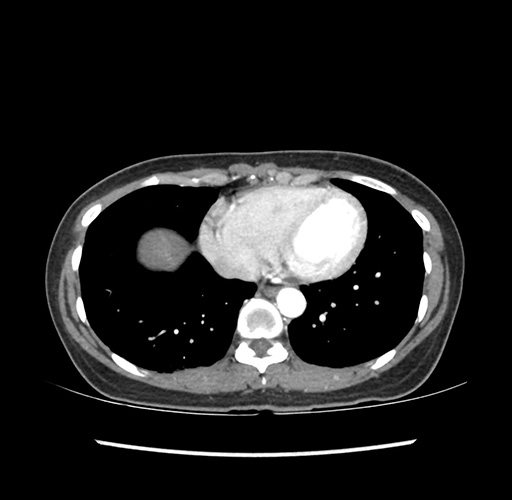

Imaging Analysis

Look through the patient's CT scan to identify any areas of concern for the necessary procedure.

Based on your CT findings, which issue(s) would give reason for "planned slowing down moment(s)" in this case?